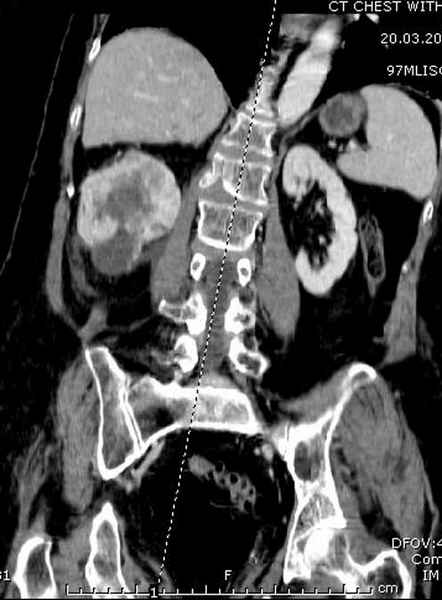

Со слов, больная ничем не болела, только последние 3 месяцев чувствовала боли в бедренной области. КТ брюшной полости подтвердил увеличенную правую почку. (5-6)

Для предупреждения кровотечения во время рассверливания, за день до операции провели эмболизацию сосудов питающий метастаз. http://radiology.rsnajnls.org/cgi/reprint/150/3/673.pdf (7-11, 12-15-16)

С минимальным рассверливанием и ретроградным методом провели остеосинтез бедра 12 мм гвоздем. (17-20)

Кровопотеря во время операции меньше 100 мл.

Больная выписана, взятый во время рассверливания материал изучается.